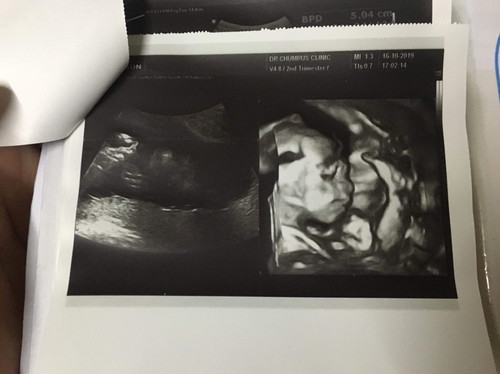

หมอบอกน้องดิฟฟี่ 3 โลกว่าแล้ว อีก3 วันมาดูกันถ้าไม่เจ็บท้องคลอดก็ผ่าเลยจ้า แม่ๆคิดว่าไงคะไม่อยากผ่าค่ะ ตอนนี้ 38 สัปดาห์ 4 วันแล้วค่ะ จะรอไปจนกว่าจะเจ็บท้องและคลอดเองดีมั้ยคะ ดีไหมคะ ....? ? กำหนดคลอดวันที่ 1 กพ. 63 แต่ตอนนี้ 22 มค. 63 นน.น้อง 3.45 โล จะรอจนกำหนดดีมั้ยคะ แม่ๆคิดว่าอันตรายมั้ยคะ เพราะตอนนี้ยังไม่ได้รู้สึกเจ็บท้องอะไรเลยค่ะ ฝากหมอพิเศษด้วยค่ะ